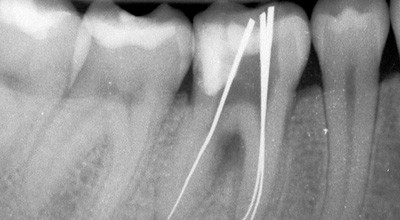

Der andere Fall behandelt einen etwas komplexeren Fall. Hier stellte sich der 42-jährige Patient vor, da die Krankenkasse seine geplanten Kronen an den Zähnen 45, 46 und 47 nach gutachterlicher Untersuchung nicht genehmigte, weil die Wurzelkanalfüllung in der mesialen Wurzel an Zahn 47 nicht die korrekte Länge aufwies. Die Wurzelkanalfüllungen waren seit mehr als fünf Jahren in situ und der Patient hatte keinerlei Beschwerden. Dies wurde auch durch die Röntgenerstaufnahme belegt, wo keinerlei entzündliche Veränderungen erkennbar sind. Nach entsprechender Aufklärung und Darstellung der Kanäle unter dem OP-Mikroskop wurde der Versuch unternommen, die Wurzelkanalfüllung an Zahn 47 zu revidieren. Die mesialen Wurzelkanäle waren dabei initial lediglich mit C-Feilen ISO 06 (VDW, München) sukzessiv tiefer zu katheterisieren. Nachdem

die endometrische Längenbestimmung (Raypex 4, VDW) keinen Hinweis auf eine Perforation gab, konnte mittels der Messaufnahme der ungünstige Kanalverlauf anhand der Deformationen der Silberstifte belegt werden. Nach Auf-bereitung mit NiTiflex-Handinstrumenten (Dentsply Maillefer, Ballaigues, Schweiz) und erfolgter Obturation genehmigte der Gutachter schließlich die Kronenversorgung der entsprechenden Zähne (Abb. 17–19).